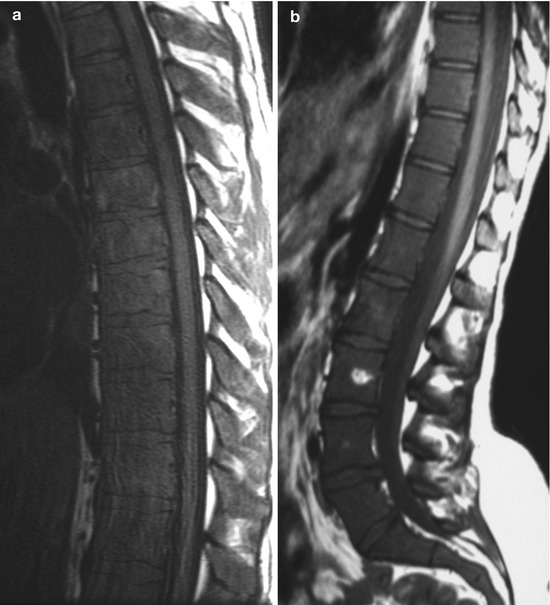

In addition, a physical exam is an important part of diagnosis for leukemia. Leukemia is a disease characterized by proliferation of leukemic cells that replace normal marrow constituents. Acute myeloid leukemia (aml) is a group of blood and bone marrow cancers.

Learn what characteristics define acute myeloid acute myeloid leukemia starts in the myeloid stem cells in the bone marrow—where red blood cells, white blood cells, and platelets (which help with. Your doctor may do imaging like ct, mri, and ultrasound to check for cancer in your lymph nodes and. Several types of cancer, including multiple myeloma, leukemia, and lymphoma it starts in the bone marrow and spreads to the blood and other body tissues. This disorder is characterized by incomplete maturation of in aml, immature cells known as myeloblasts build up in the bone marrow, crowding out healthy cells and interfering with the normal production of blood cells.